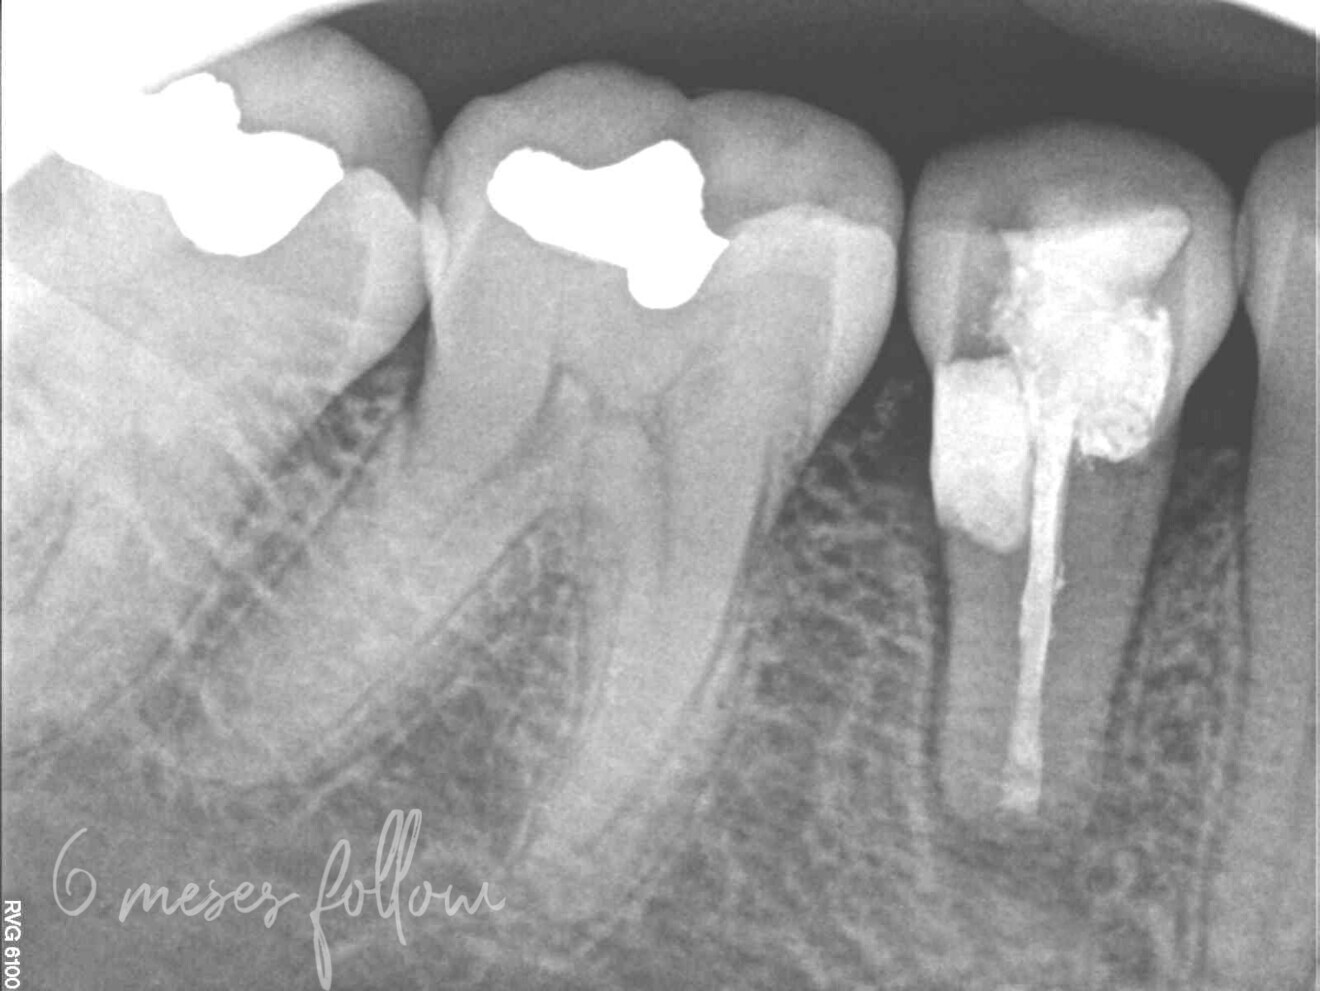

Fig. 2: Periapical radiograph of the initial situation.

A 38-year-old woman presented to the dental practice complaining of discomfort in the area of tooth #45. Her symptoms worsened with chewing. The patient’s clinical history was not contributory. She reported that root canal therapy had been performed on tooth #45 owing to caries and that she had undergone orthodontic treatment seven years earlier. The clinical tests found pain on percussion and a distal probing pocket depth of more than 3 mm.

The radiographic examination showed periapical radiolucency and a radiolucent lesion in the cervical area of the tooth (Figs. 1 & 2). To determine the extent and depth of the lesion, a CBCT scan was performed (Fig. 3). Based on the CBCT images and 3D reconstructions, a diagnosis of Heithersay Class III external cervical invasive root resorption (ECIR) was determined in an endodontically treated tooth with symptomatic periapical periodontitis. The patient was informed of the diagnosis, treatment plan alternatives and prognosis of the case.